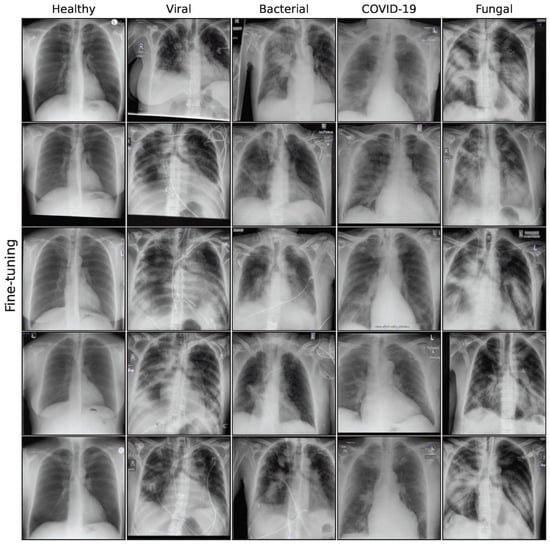

3.2. Image Synthesis

This subsection describes the generative models used in this work. We utilize a special GAN model, a Denoising Diffusion Probabilistic Model (DDPM), and 3 different fine-tuning approaches for a Stable Diffusion [34] model: standard fine-tuning, Low-Rank Adaption (LoRA), and DreamBooth. Our aim is to compare the performance of a GAN model to more recent diffusion-based architectures, building on the GAN proposed in Schaudt et al. [35]. Figure A2 in the Appendix A shows a collection of synthetic images for all generative models.

Figure A2. Sample synthetic images from all classes and methods.